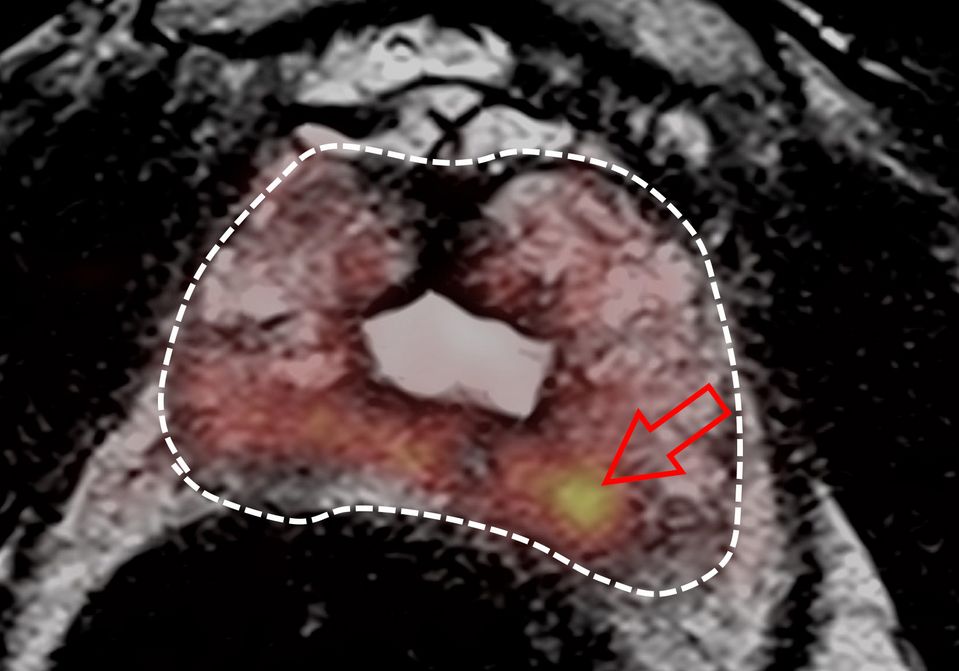

Man erhält hochauflösende, detailreiche Bilder, auf denen man Tumoranteile sehr gut von umgebendem gesunden Prostatagewebe abgrenzen kann. Man beurteilt dabei:

- Die Form und innere Struktur der Prostata. Tumore zeichnen sich dabei durch eine Störung der Prostataarchitektur aus. (T2-Wichtung)

- Die Zelldichte der Prostata. Tumore haben aufgrund ihres Wachstums eine höhere Zelldichte als gesundes Gewebe. (Diffusionswichtung)

- Die Durchblutung der Prostata. Tumore sind besser durchblutet als normales Prostatagewebe. Hierfür ist die Gabe von Kontrastmittel über eine Vene erforderlich. (Perfusionsmessung)

Die Dauer der Untersuchung beträgt ca. 30min. Durch eine standardisierte Auswertung dieser drei Parameter (sog. PI-RADS 2.1 Schema) können behandlungswürdige Prostatakarzinome mit einer Genauigkeit von ca. 90% entdeckt, aber auch, und dies ist genauso wichtig, sicher ausgeschlossen werden. Dem Urologen kann dann genau die Größe und Lage des mutmaßlichen Tumorherds mitgeteilt werden.